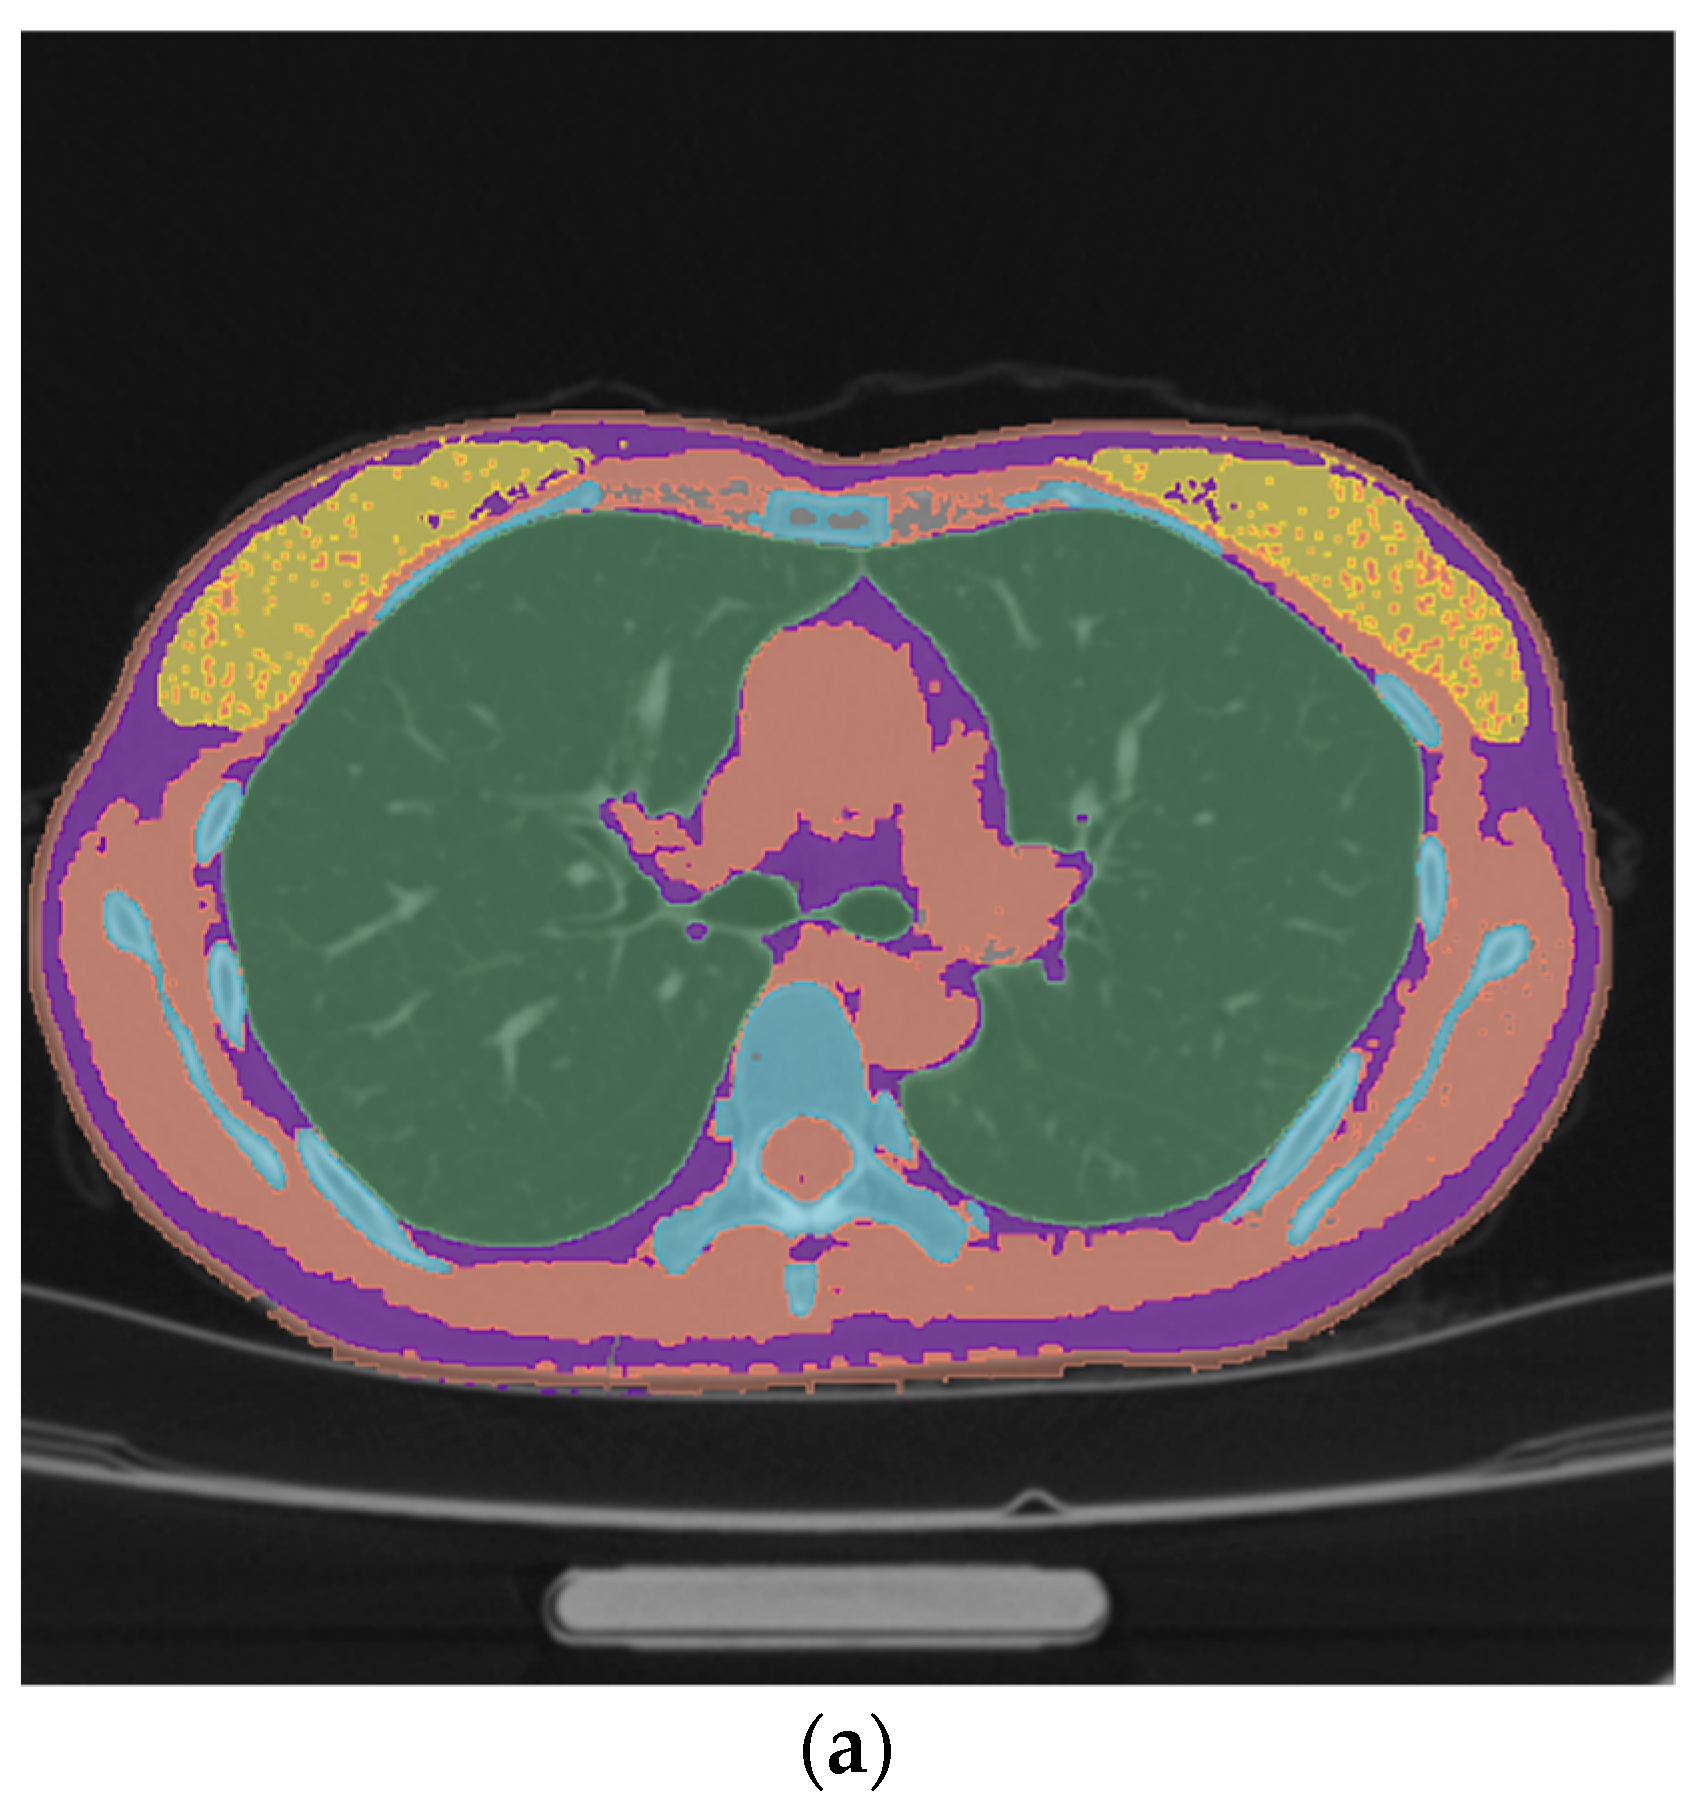

3.1. Voxelized Chest Models of Patients